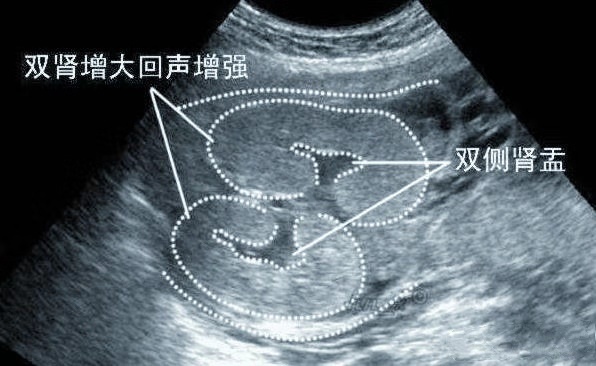

那么,什么就叫做双肾盂分离,是什么原因导致,胎儿双肾盂分离,真的预示胎儿性别吗?今天美妈就来给大家梳理一下。胎儿双肾盂分离的原因有哪些?所谓的肾盂,是指肾与输尿管的连接处;而肾盂分离,就是肾脏的尿液无法正常地流入膀胱。当尿液积存到一定的时候,就会出现肾盂分离。胎儿肾盂分离的原因有两个,一个是由于输尿管的一部分狭窄而导致尿液流动停滞,另一个是积存在膀胱中的尿液朝肾脏逆流而造成。

怎么判断肾盂分离是否正常?胎儿双肾盂分离多半发在孕中期与孕晚期。孕妈听到胎宝宝肾盂分离或许有会很焦虑,其实不必过于担心。胎儿肾脏轻度分离是很常见的,据统计显示,100个胎儿之中就有一个胎儿会出现肾盂轻度分离的情况,而且大部分会随着孕周增长而逐渐消失。正常来说,肾盂分离<10mm,为生理性,不必特别处理,孕妈定期检查就好。但是怀孕30周后,肾盂分离≥10mm,则可能要考虑肾积水了,一个小时后需要再进一步确认,检查结果还是一样的话,那医生就要给胎儿做相关的检查,必要时进行治疗,据说这种情况600-800个胎儿之中有1个,而且有99?小宝宝在出生后可治好。像题主这样,孕早期就有,孕晚期还没消失而且肾盂分离≥10mm,则要跟医生沟通一下了。

孕期胎儿双肾盂分离,多半怀“小公子”?确实,与女宝宝相比,男宝宝发生双肾盂分离概率比女宝宝高4-5倍!这是由于男宝宝的尿道较长,膀胱内压更高,比女宝宝更容易憋尿,因而更容易引发双肾分离。虽然概率较大,但还有40?机会生小棉袄,所以不要像小樱那样就此轻易下结论!